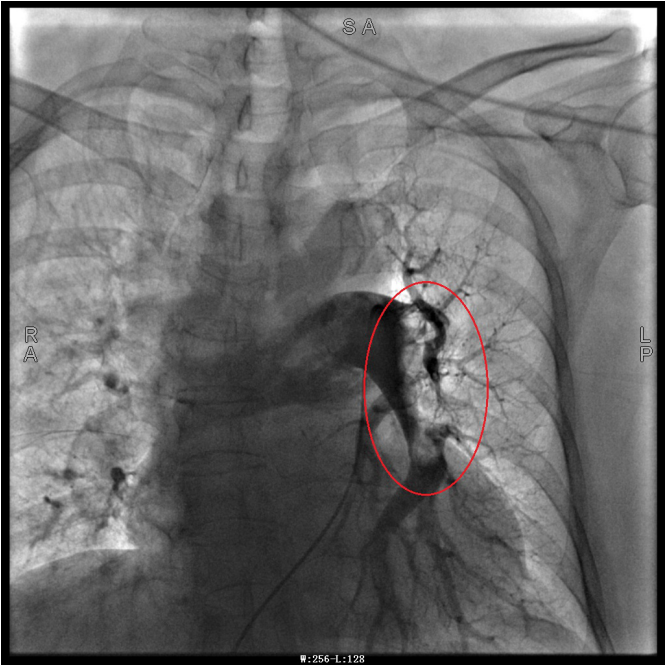

一站式”介入手术,即两种介入手术一次完成。在过去,肺动脉血管+心脏血管手术需要呼吸与危重症医学科、心血管内科团队联合完成,现在通过“一站式”介入,由一人便可独立完成。据了解,重庆市璧山区人民医院心血管内科成功完成渝西地区首例”一站式”介入手术:冠脉造影+右心导管+肺动脉造影+肺动脉导管内溶栓术。 谭婆婆今年已经72岁了,因“突发意识障碍2次”到璧山区人民医院神经内科治疗。谭婆婆没有基础心脏病病史,但近段时间活动耐量明显下降,稍做活动就出现呼吸困难。入院后查BNP及心脏彩超均未提示明显异常,查D二聚体明显升高,经心血管内科周波医师会诊后转入科室继续治疗。在心血管内科主任、内科学(心血管病)博士于长青的指导下,周波医师成功完成医院首例“一站式”微创介入手术。在影像中,可以清晰地看到堵塞的血管经溶栓治疗后,重新畅通无阻,流动起支撑生命的血液。 肺动脉造影技术是目前诊断肺动脉栓塞的“金标准”,在全程心电监护下,通过股静脉或者颈内静脉置入鞘管后,利用导丝引导,将造影导管送入肺动脉;可在左/右肺动脉主干及其左右分支内,分别进行肺动脉造影或选择性肺动脉造影,存在栓塞的肺动脉血管在造影剂注入后即会显示出充盈缺损、充盈缓慢、或者血管显影模糊,严重栓塞的肺动脉血管甚至会出现血流截断征象。 肺动脉导管局部置管溶栓术是通过肺动脉造影确定堵塞的肺动脉部位,然后导管尖端置于血栓处,将尿激酶、链激酶或重组组织型纤维蛋白溶酶原激活剂直接注入血栓处,新鲜血栓在足量的溶栓剂作用下溶解。肺动脉内局部用药特别是小剂量时可减少出血并发症。 该项技术对医生手法及设备都有极高的要求,在导管通过右心室至主肺动脉时,极易出现室性心律失常等紧急状况,同时患者溶栓后有突发脑出血、消化道大出血等风险,难度较大,不仅需要引导病人呼吸配合,还需配备专业抢救设施。 璧山区人民医院成功开展该项技术,在整个渝西地区尚属首例。该技术为不明原因的呼吸困难或不明原因晕厥患者患者提供了一项全新的诊疗手段,明确患者是否存在肺动脉血栓,同时可诊断是否有肺动脉压力升高,是否行急诊溶栓治疗具有指导意义,对延长患者生命、改善患者预后、提高患者生活质量都起到了极大的帮助。 注明:第一张、第二张为术前图像 第三章未标注图像为术后图像